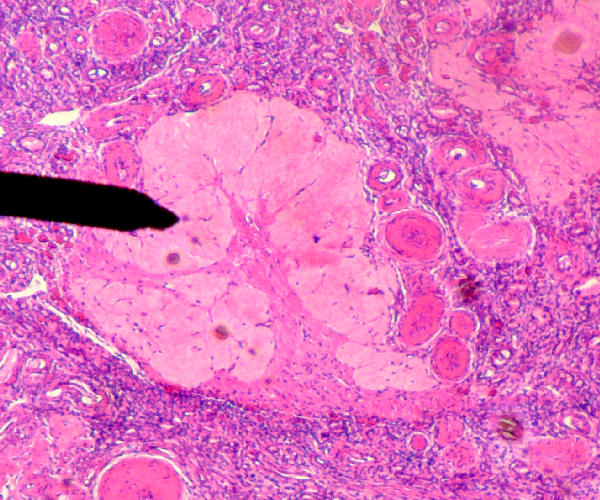

Source: Corpus_albicans.JPG